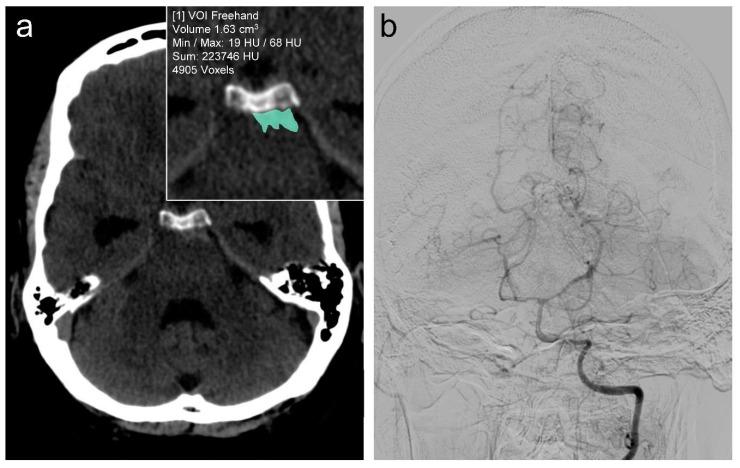

The benign nature of perimesencephalic subarachnoid hemorrhage (pmSAH) can be challenged by the occurrence of complications. Given the limited prognostic value of established clinical parameters for the development of complications in patients with pmSAH, this study evaluates the potential of volumetric hemorrhage quantification for risk assessment and the evaluation of the clinical outcome. : In this retrospective single-center study, we analyzed all consecutive patients diagnosed with pmSAH between 2010 and 2023 at a tertiary care academic medical center in Germany. The volumetric quantification of the hemorrhage in cm was performed using non-contrast CT imaging. The occurrence of clinical complications, including hydrocephalus, vasospasm, and delayed cerebral ischemia (DCI), were assessed. Clinical outcomes were determined by the Glasgow Outcome Scale (GOS) at discharge. Multivariable logistic regression models were used to assess the correlation between quantified hemorrhage volumes and the occurrence of complications and clinical outcomes (GOS) controlled for other variables such as age, sex, cardiovascular risk factors, clinical symptoms, and the modified Fisher scale. : A total of 82 patients (58.5% male, 54.8 ± 12.1 years) were enrolled. The median World Federation of Neurosurgical Societies (WFNS) score for all patients at admission was 1.0 (IQR 1.0-1.0). During the clinical course, hydrocephalus occurred in 29%, vasospasm in 14.6%, and DCI in 8.5% of all patients. Hemorrhage volume quantification was found to be the strongest independent predictor for hydrocephalus (OR 1.28; 95% CI 1.02-1.61; = 0.032) and vasospasm (OR 1.25; 95% CI 1.07-1.46; = 0.007) and showed a high predictive accuracy in ROC analyses (AUC = 0.77 and 0.76, respectively). Conversely, neither clinical parameters nor the modified Fisher scale were associated with these complications. A higher hemorrhage volume was also significantly correlated with a worse functional outcome (GOS; = -0.07, CI: -0.12--0.02, = 0.021). In patients with pmSAH, the volumetric quantification of hemorrhage may be an adequate prognostic parameter regarding the occurrence of hydrocephalus and vasospasm. In addition, the quantitative assessment of hemorrhage volumes was strongly associated with clinical outcomes in these patients. Despite the generally benign nature of pmSAH, this imaging biomarker could improve individualized clinical management strategies and inform about the risk for the occurrence of complications.

中脑周围蛛网膜下腔出血(pmSAH)的良性本质可能会受到并发症发生情况的挑战。鉴于已有的临床参数对pmSAH患者并发症发生情况的预后价值有限,本研究评估了出血体积定量在风险评估和临床结局评估方面的潜力。:在这项回顾性单中心研究中,我们分析了2010年至2023年期间在德国一家三级医疗学术医学中心连续诊断为pmSAH的所有患者。使用非增强CT成像对以立方厘米为单位的出血进行体积定量。评估包括脑积水、血管痉挛和迟发性脑缺血(DCI)在内的临床并发症的发生情况。临床结局由出院时的格拉斯哥预后量表(GOS)确定。使用多变量逻辑回归模型评估定量出血体积与并发症发生情况和临床结局(GOS)之间的相关性,并对年龄、性别、心血管危险因素、临床症状和改良Fisher分级等其他变量进行控制。:共纳入82例患者(男性占58.5%,年龄54.8±12.1岁)。所有患者入院时世界神经外科医师协会(WFNS)评分中位数为1.0(四分位间距1.0 - 1.0)。在临床过程中,所有患者中有29%发生脑积水,14.6%发生血管痉挛,8.5%发生DCI。发现出血体积定量是脑积水(比值比1.28;95%置信区间1.02 - 1.61;P = 0.032)和血管痉挛(比值比1.25;95%置信区间1.07 - 1.46;P = 0.007)最强的独立预测因素,并且在ROC分析中显示出较高的预测准确性(曲线下面积分别为0.77和0.76)。相反,临床参数和改良Fisher分级均与这些并发症无关。较高的出血体积也与较差的功能结局(GOS;P = -0.07,置信区间:-0.12 - -0.02,P = 0.021)显著相关。在pmSAH患者中,出血体积定量可能是关于脑积水和血管痉挛发生情况的一个合适的预后参数。此外,出血体积的定量评估与这些患者的临床结局密切相关。尽管pmSAH总体性质为良性,但这种影像学生物标志物可以改善个体化临床管理策略,并告知并发症发生的风险。